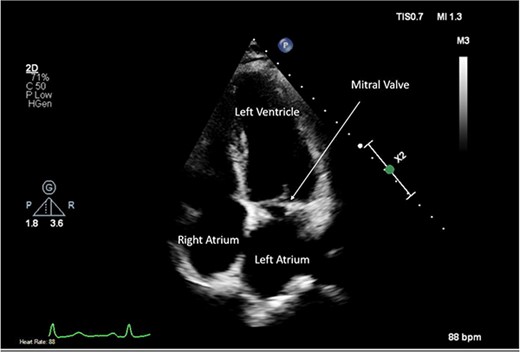

A CTPA was undertaken on Day 2, which excluded pulmonary embolism but confirmed bilateral peri-hilar consolidation and pleural effusions consistent with pneumonia. However, her pulmonary artery was dilated at 32 mm indicative of potential heart failure. On Day 5 of her ICU stay, a transthoracic echocardiogram was undertaken that revealed there to be severe mitral regurgitation including a mobile echogenic mass attached to the underside of the anterior mitral valve leaflet consistent with a vegetation (Figs 1 and 2).

Pre-operative TTE with Doppler depicting mitral valve with vegetation (labelled).

Intra-operatively, femoral–femoral bypass was established and a 3 cm windsock vegetation was found with a 1.5 × 1.5 cm hole at the aortic inlet on the annular junction. The vegetation travelled from the LV to LA as shown in Figs 3 and 4. The vegetation was excised and the valve debrided, which resulted in moderate regurgitation from severe. Hence, a further 26 mm Physio II ring was placed resulting in no mitral regurgitation. The excised vegetation is shown in Fig. 5 and the post-op TTE images are shown in Figs 6 and 7.